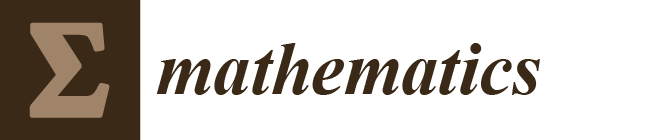

3.1. Pneumonia Dataset

3.2. COVID-19 Dataset